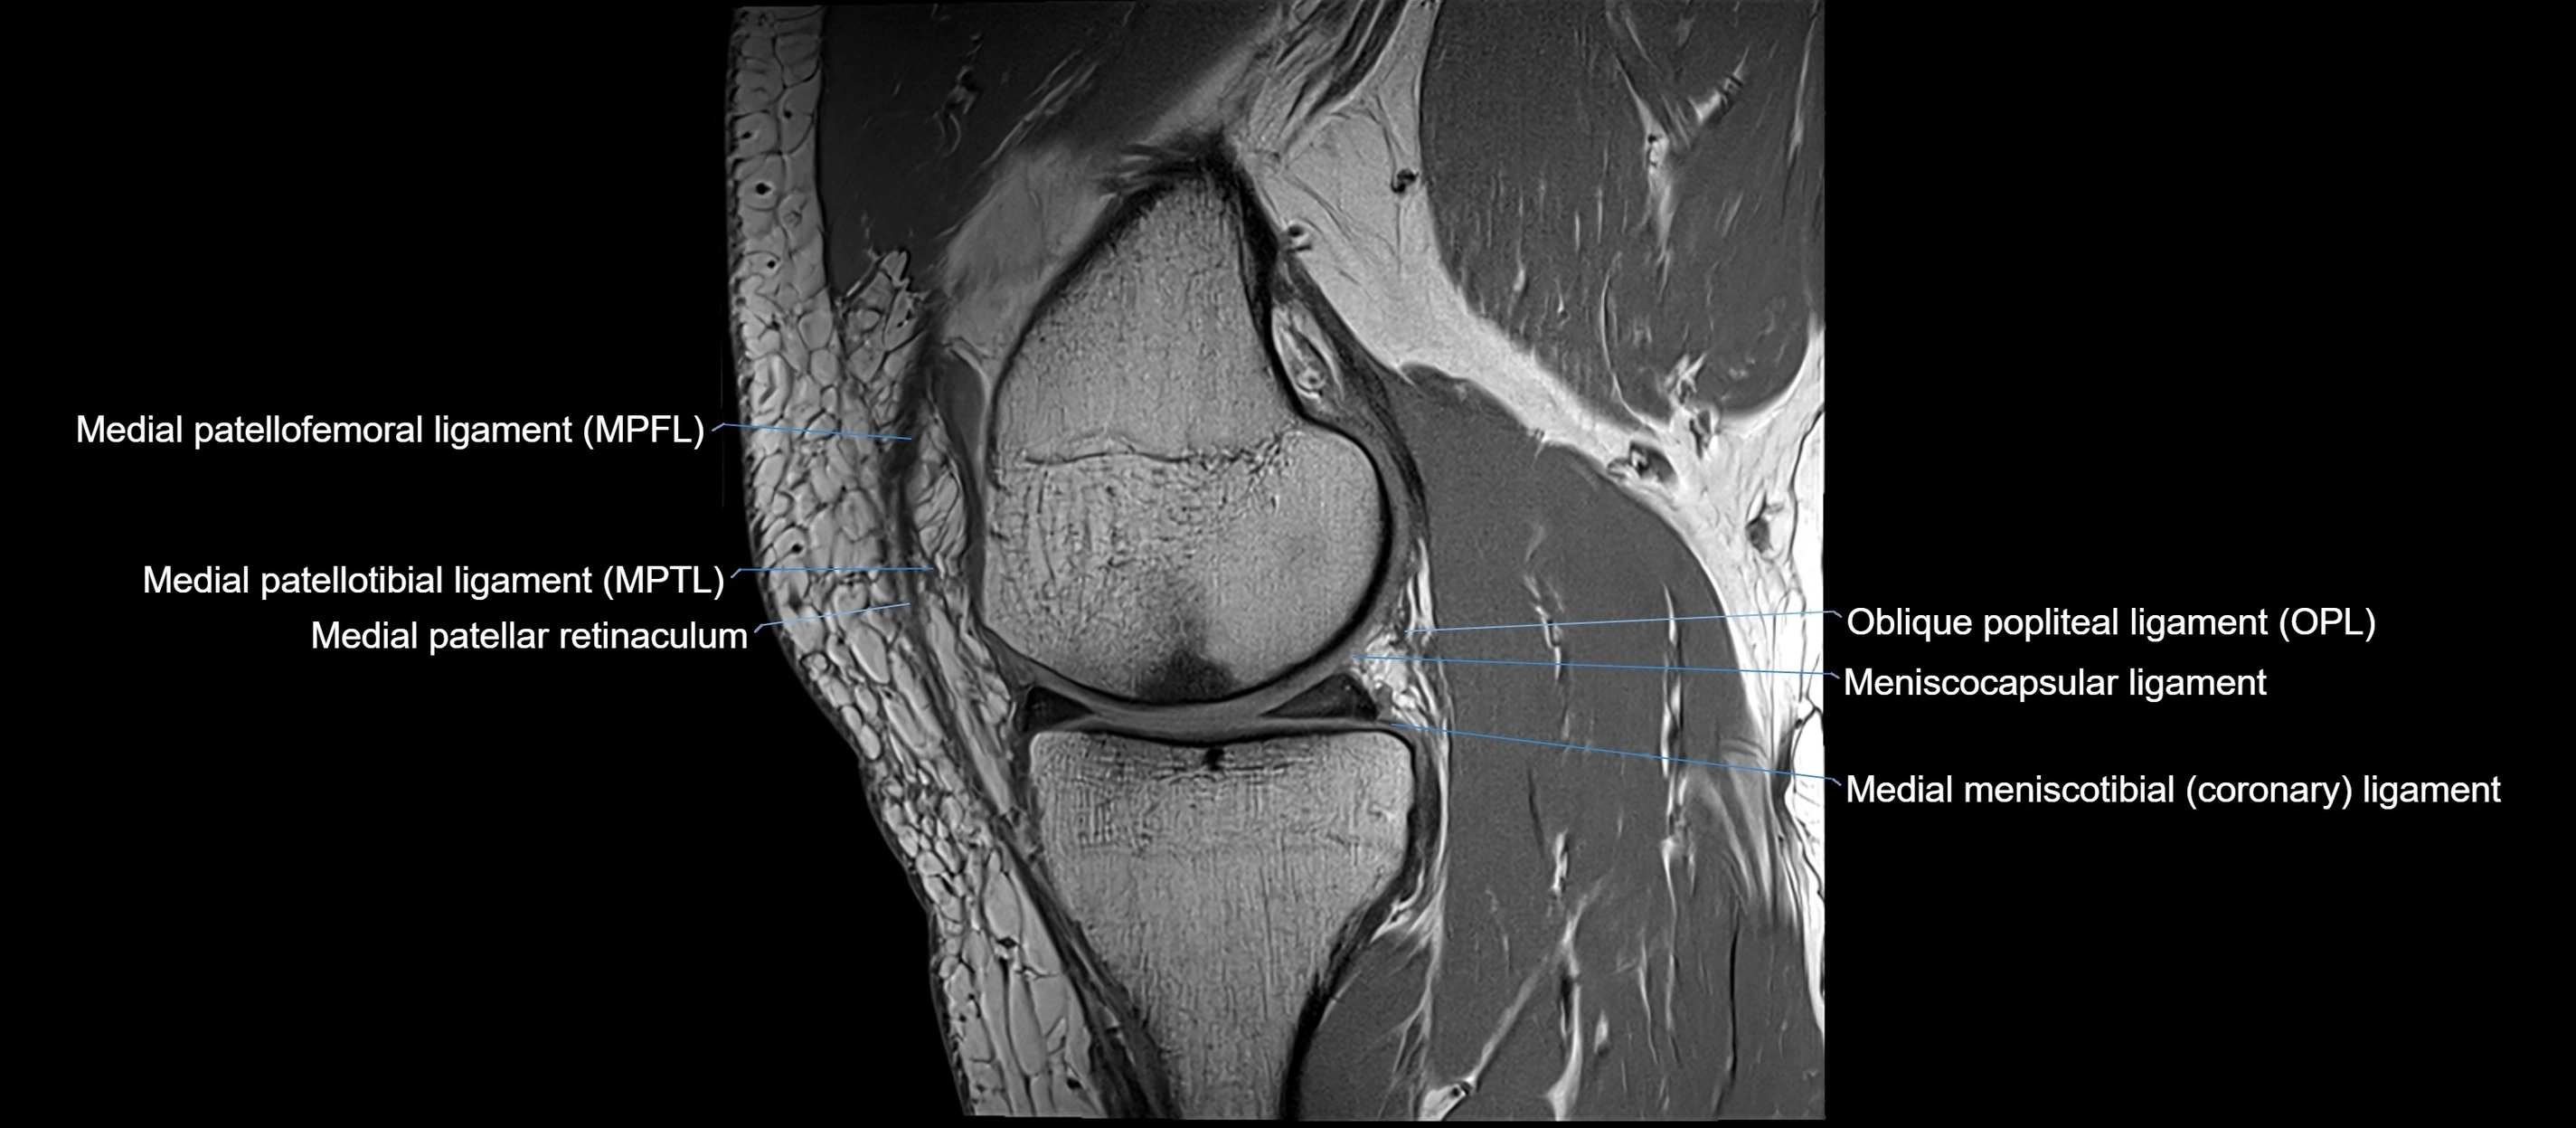

MRI images

image